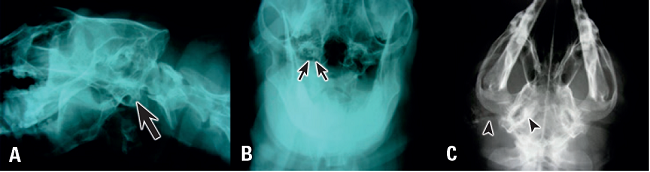

El estudio radiográfico requiere sedación profunda o anestesia. Se recomiendan las proyecciones lateral oblicua del cráneo con el lado enfermo apoyado en el chasis, ventro dorsal del cráneo y frontal con la boca abierta, con el colimador centrado en la faringe y tirando de la lengua hacia afuera para eliminar la interferencia del tejido blando. Los cambios sugerentes de OM incluyen: radio-opacidad en la bulla timpánica que suele producirse porque existe pus caseificado en su interior o crecimiento de tejido granulomatoso, neoplásico o pólipos (Pratschke 2003), es posible observar también esclerosis de la pared de la bulla timpánica o lisis de esta estructura (Figura 3-A y B). Muchas veces los Rayos X hacen evidente el grado de hiperplasia y calcificación del conducto auditivo externo que caracteriza la OEC (Figura 3-C), hallazgo muy importante porque también es una indicación de la intervención quirúrgica en OEC.